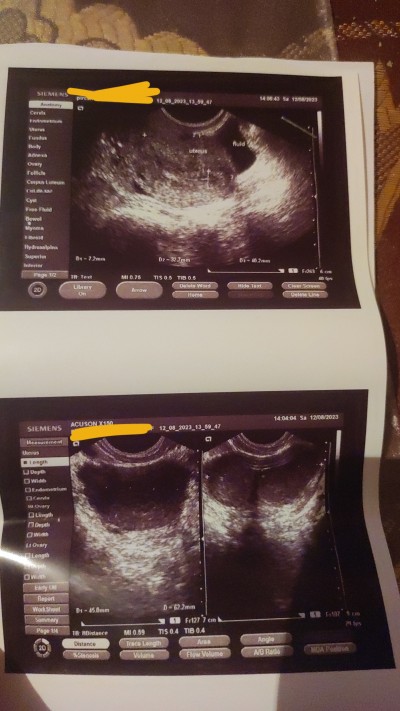

Selam kzlar ben ayn 12si gibi ultrasyona gittim boyle sekil verdi bana gebelik kesesi gorunuyormu? Bide adetime hala var bana doktor soylediki hcg kan testi ver siz ne goruyorsunuz resmde?

Kese görmüyorum ben. Regliniz 1hafta gecikmeden test yapmayın hayal kırıklığı olmasın Hakkınızda hayırlısı olsun

Bildiğim kadarıyla kese böyle olmuyor ama sen yinede gününü bekle hayal kırıklığı yasama canım hayırlısı olsun hakkinda

Kese göremedim ben adetinize daha var ise beklemek daha iyi olur sonunda üzülmemek için beta verdiniz mi

Zaten kzlar bana soylediki doctor kese 3.4hafdalinda gozuke bilir burda eger varsa 1bucuk haftalk gozukmezki